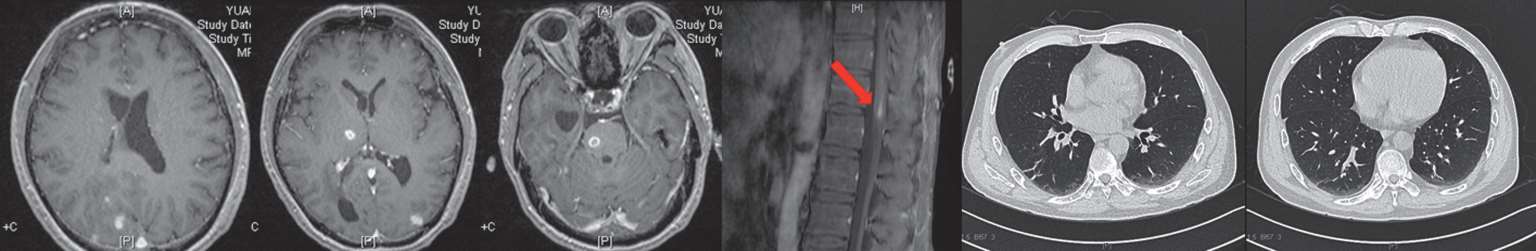

8月22日复查头颅及胸腰椎增强MRI示病灶均较前明显好转(图2-8)。患者已能对答切题及按照指令动作,GCS评分15分,拔除胃管后可自行进食。8月23日,调整方案为头孢曲松2 g ivgtt q12h联合青霉素640万U ivgtt q8h继续抗链球菌治疗。9月30日复查腰穿,脑脊液较前进一步好转(表2-1)。10月9日复查头颅、胸腰椎增强MRI及肺CT,病灶均进一步缩小(图2-9)。

图2-8 2018年8月22日头颅及胸腰椎增强MRI

图2-9 2018年10月9日头颅、胸腰椎增强MRI、肺平扫CT

在住院期间,患者7月30日上腹部增强CT曾发现左肾占位性病变,考虑肿瘤可能,待病情较为稳定后,8月27日行肾脏增强CT(图2-10)示左肾上极占位,考虑透明细胞癌可能。请泌尿外科会诊,考虑患者目前手术风险较大,家属也暂拒绝手术,故进一步随访中。因此综合分析该患者的病情,考虑是肾脏肿瘤基础上发生的播散性中间链球菌感染。

图2-10 2018年8月27日肾脏增强CT